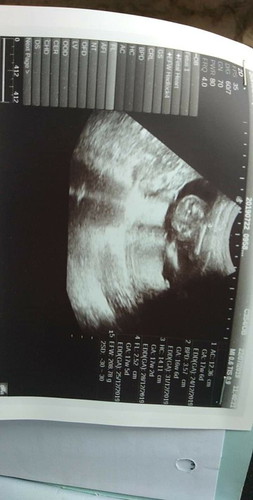

ตามหัวข้อเลยจ้า อยากรู้ว่าน้ำหนักน้อยกว่าเกณฑ์ไหมคะ ตอนนี้17 w 3D

ไม่น้อยค่ะแม่ 208.78 กรัม ลองดูเกณฑ์จากตารางค่ะแม่